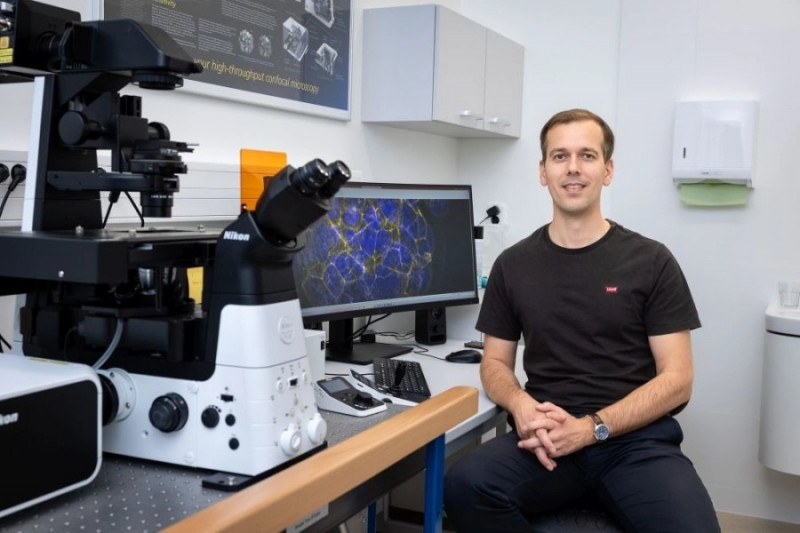

#ReprodukčníChirurgie #Plodnost #Gynekologie